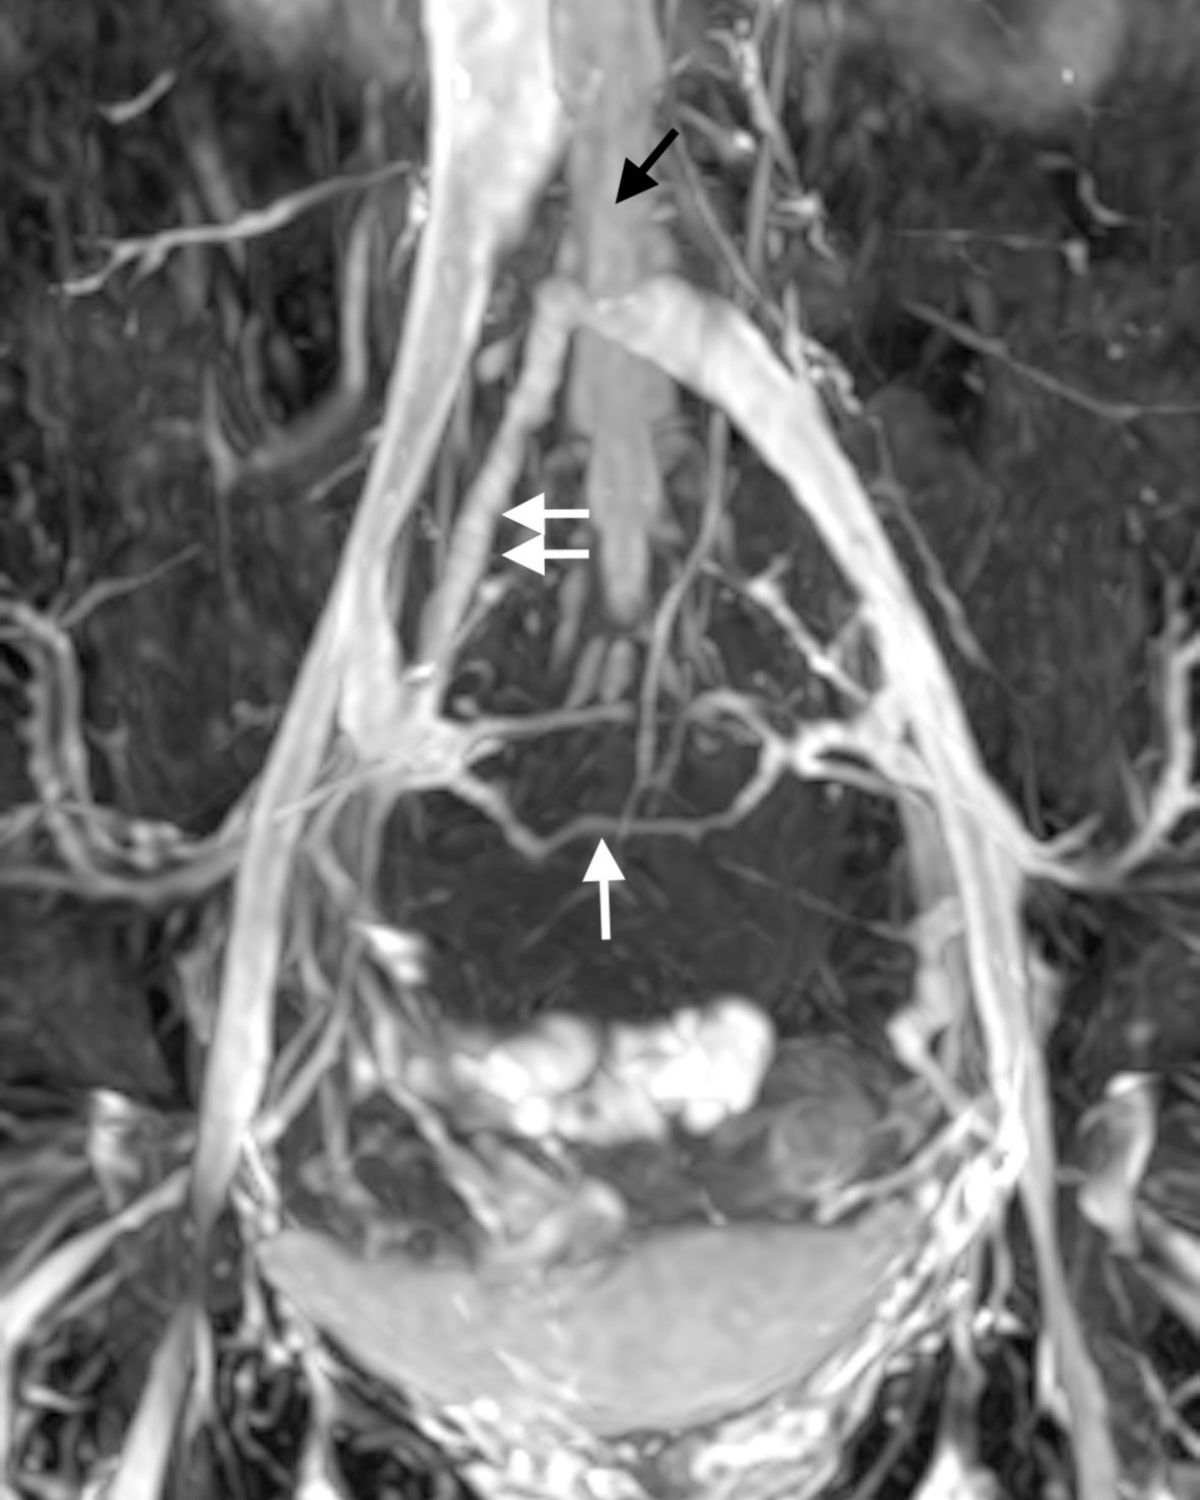

圖二:白色箭頭:擴大、逆流的左生殖靜脈 黑色箭頭:因血流過多造成的子宮靜脈曲張,常引起下腹痛

過多的骨盆腔血流也會流竄到身體的其他地方包括骨盆腔底部的會陰以及腰椎後方的血管。

圖三:因為退化的左生殖靜脈 (黑色星號 *)造成過多血流,而使得髂靜脈發生血流過多產生的"相對狹窄",可以看到血流往上升,腰椎靜脈(黑色箭頭)和脊椎方向流去。

過多的血流經過會陰部(Perineal type Pelvic leak),往骨盆腔外滲出(白色箭頭)。

在無毒核磁靜造影中,可以讓病患及醫師視察到逆流及粗大的生殖靜脈及子宮/直腸/膀胱/陰道附近的扭曲的靜脈,甚至在私密處的骨盆腔靜脈滲漏。